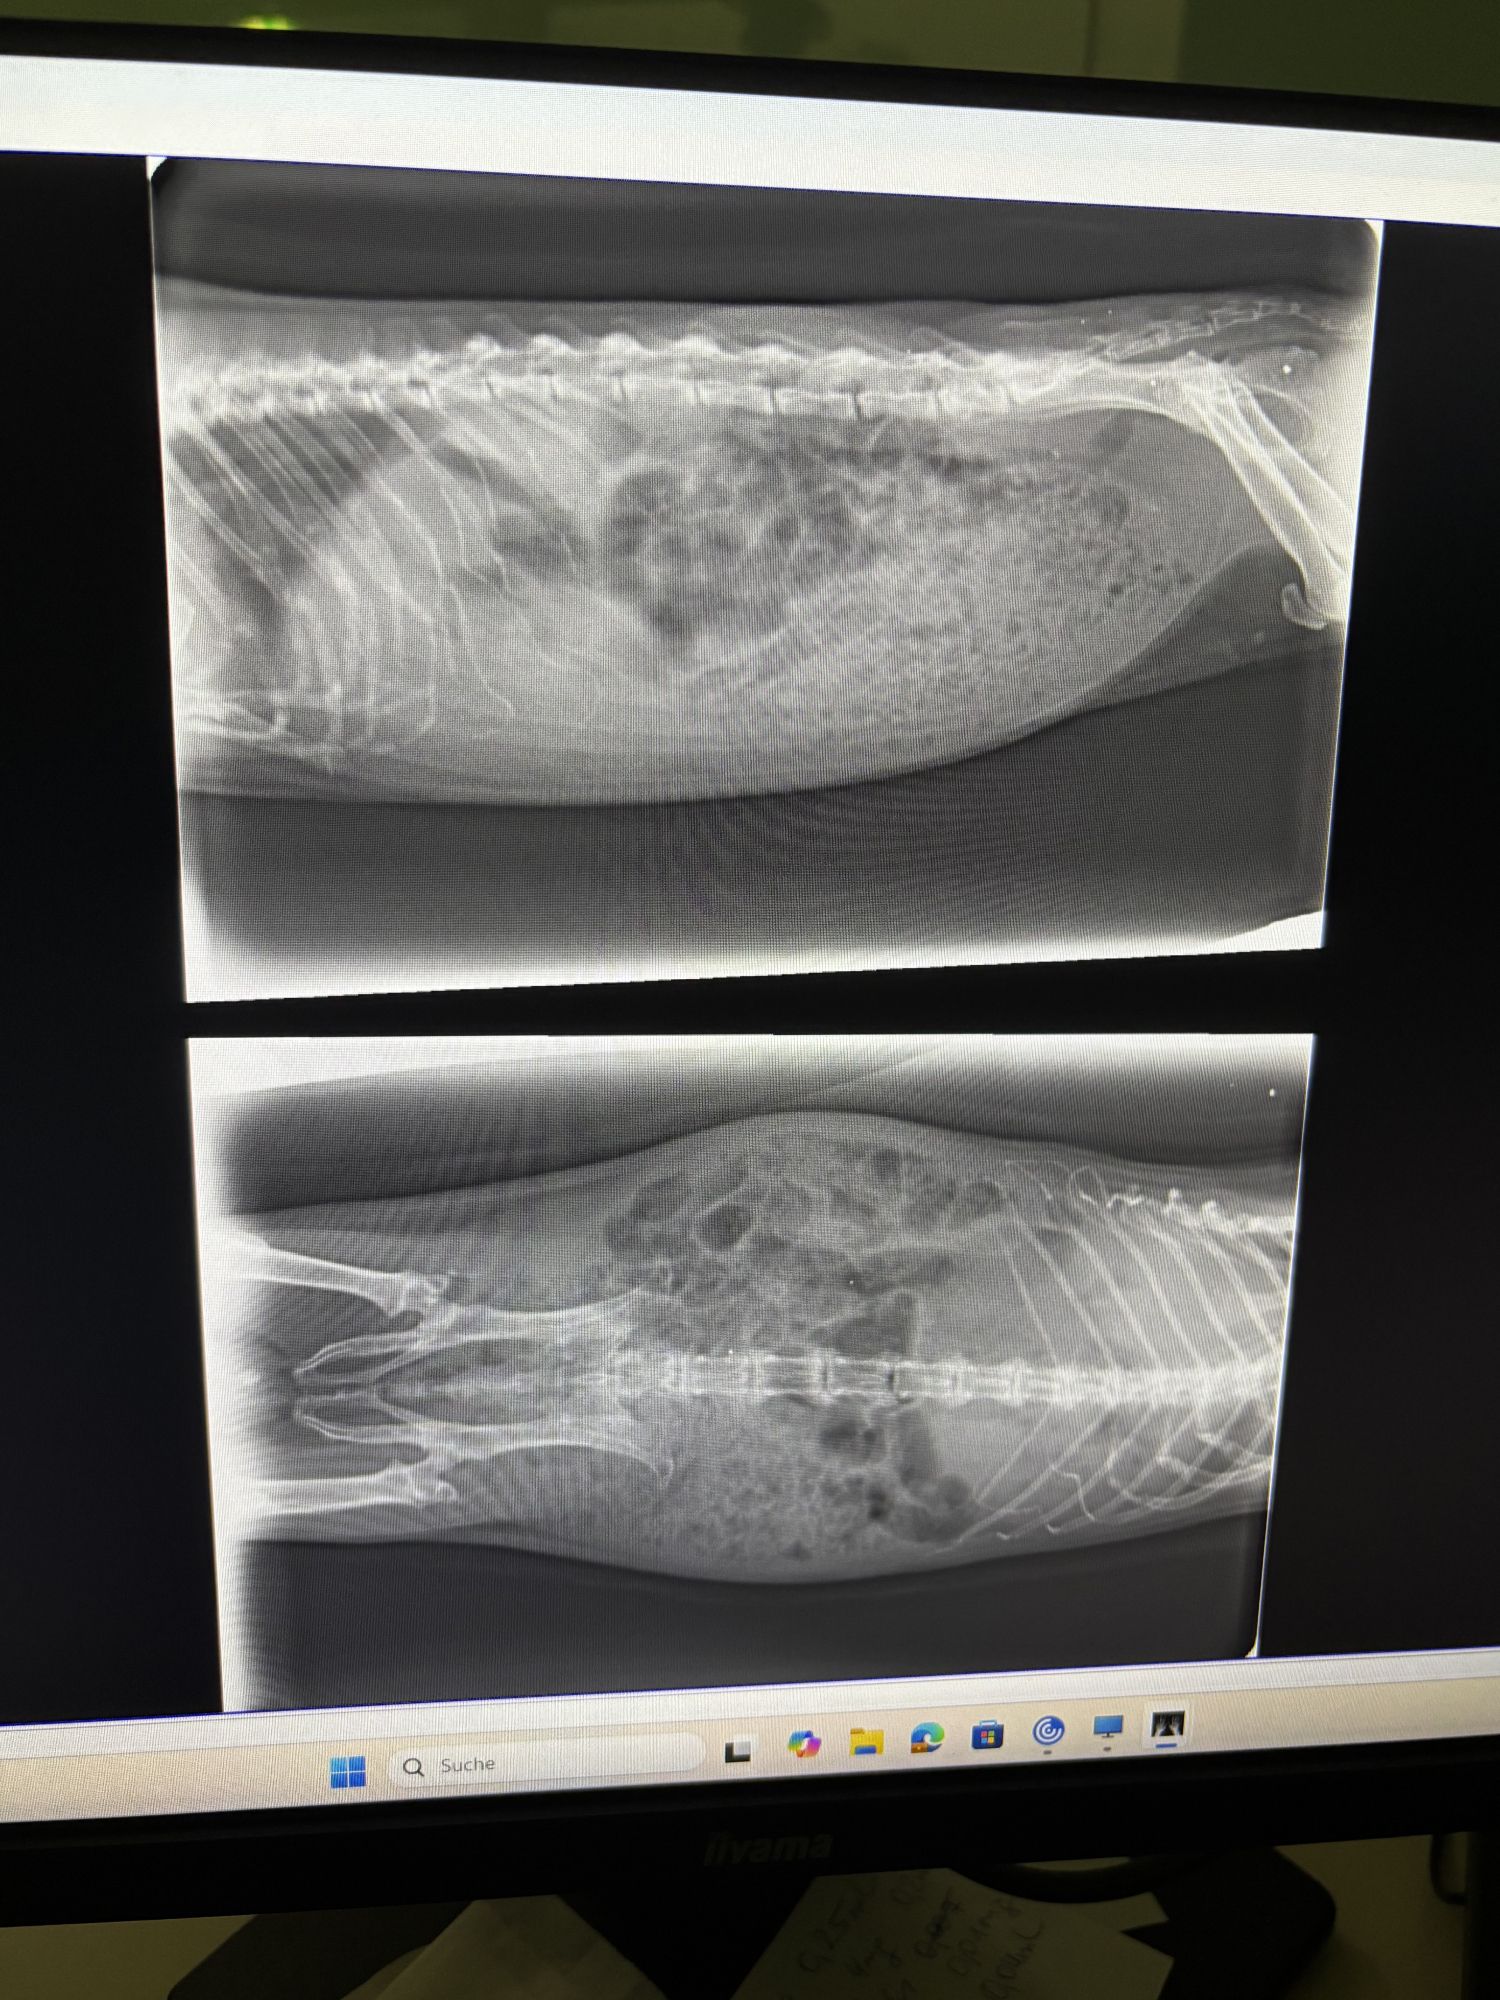

Ich hänge mal ein Bild an mit den Vergleichswerten. So wie ich es interpretiere ist auf jeden Fall ordentlich Blut im Urin. Sehn kann man davon nichts aber es ist quasi instant dunkelgrün geworden als ich draufgetropft habe.

Würde das nicht jetzt eher wieder für eine Entzündung sprechen? Was mich wieder zurückführt zur Frage, müssten die Antibiotika dann nicht geholfen haben? Ich bin grad echt ein bisschen überfordert 😅 aber so lernt man hoffentlich dazu 😊